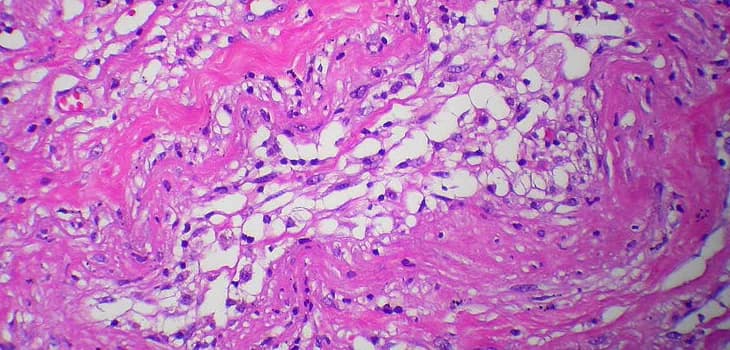

The Lipogems system utilizes adipose tissue harvested through lipoaspiration to create injectable material. The technology preserves adipose tissue integrity, maintaining its vascular network and extracellular matrix, supporting enhanced tissue integration.

Lipogems' unique advantage is maintaining the complete regenerative environment of adipose tissue, enhancing cellular vitality and regenerative capacity. The present mesenchymal cells require support from other cells and proteins to exert their healing benefits.